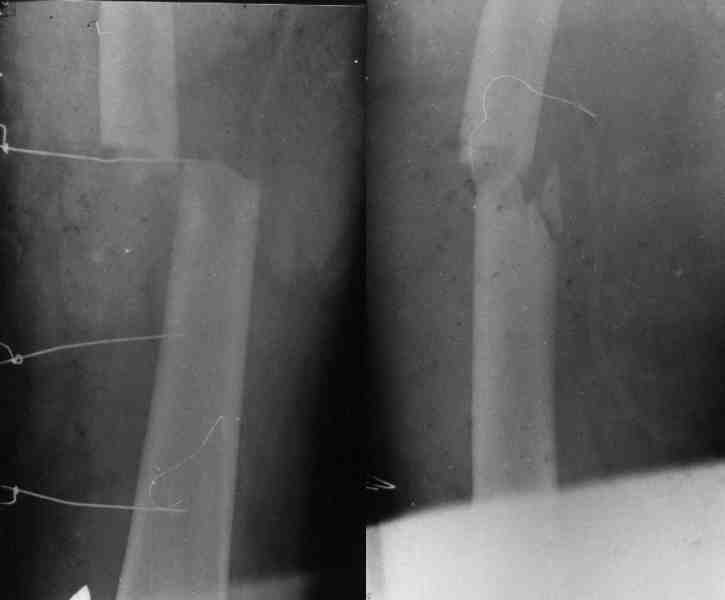

При рассверливании дистального отдела плеча будьте

осторожны, чтобы не получилось, как у моего партнера, во время установки интрамедуллярного

штифта римером раскололи вдребезги дистальный суженный бесканальный отдел плеча, после фиксация уже в двух сегментах, вот уже несколько лет не может смотреть на интрамедуллярный штифт для плеча.